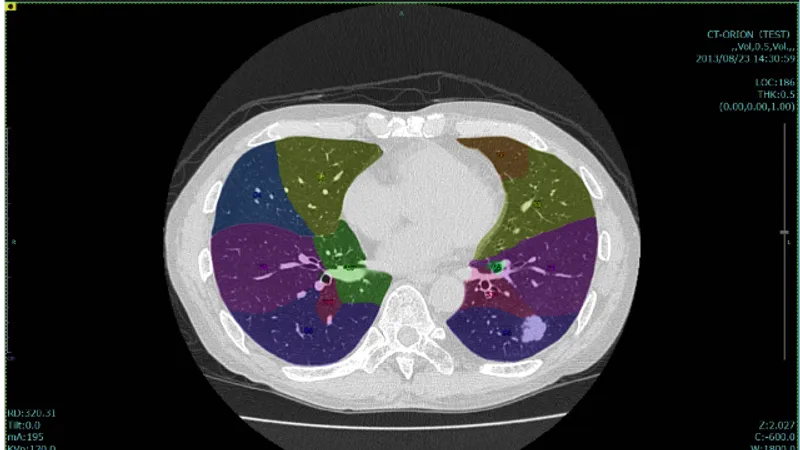

本製品の特長は以下3点です。 ① 胸部CT画像から肺結節の候補を自動で検出し、検出箇所をマークして表示します。医師は画像確認を行った後、マークされた箇所を再確認し、肺結節かどうかを判断します。 ② CT画像を3D解析する当社技術を活用し、3次元情報に基づいて肺結節の候補を検出するため、CTの断層画像だけでは見分けがつきにくい、血管に付着した結節等も検出することができます。 ③ 臓器認識技術により、肺領域を認識したうえで検出するため、胸壁に接した結節の検出も可能です。 また、SYNAPSE SAI viewer*1と併せてご使用いただくことで、結節のある箇所の肺区域ラベリングの結果を確認いただけます。 *1 SYNAPSE SAI viewer 販売名:画像診断ワークステーション用プログラム FS-V686型 認証番号:231ABBZX00028000 SYNAPSE SAI viewer用画像処理プログラム 販売名:画像処理プログラム FS-AI683型 認証番号:231ABBZX00029000